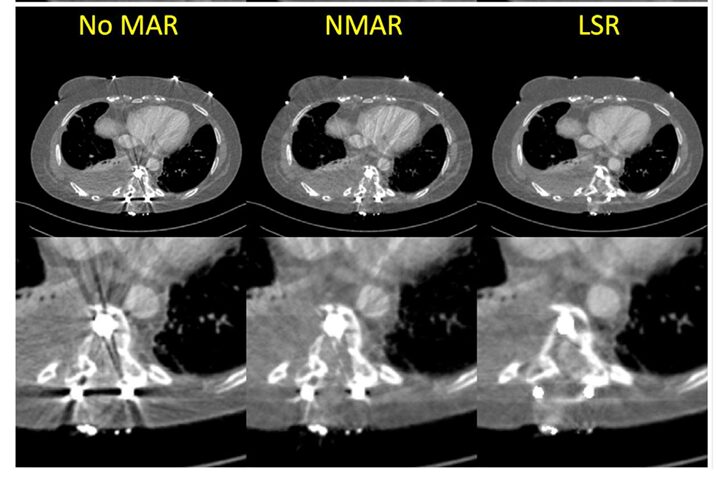

For metal artifacts, LSR was qualitatively compared to the widely-used Normalized Metal Artifact Reduction (NMAR) technique. Since no true artifact-free ground truth exists for patients with implants, evaluation was based on visual clarity.

- Qualitative Results (Figure 5): The results were striking. The “No MAR” image was heavily obscured by streaks. NMAR reduced the artifacts but left noticeable residual streaks near the metal. The LSR-corrected image demonstrated the most effective reduction, revealing clear, previously hidden anatomical structures and tissue details around the implant.

Image Description: Figure 5 shows three side-by-side comparisons for two different patients with metal implants: “No MAR,” “NMAR,” and “LSR.” The LSR images clearly show reduced streaking and improved visibility of surrounding tissues.